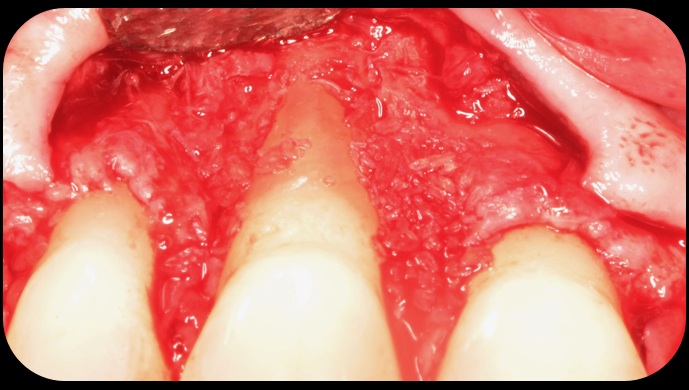

Application of enamel matrix derivative.

Fig. 4

Demineralized freeze-dried bone allograft.

Fig. 5

Evidence of clinical attachment gain.

Fig. 6

Then, too, are opportunities to prepare the site for regeneration by coupling therapies, applying an enamel matrix derivative, along with traditional bone grafts of demineralized freeze-dried bone allograft; potentially, gains in attachment with minimal probing depth and retained papilla may avoid the need for an implant (Figure 2 through Figure 7).